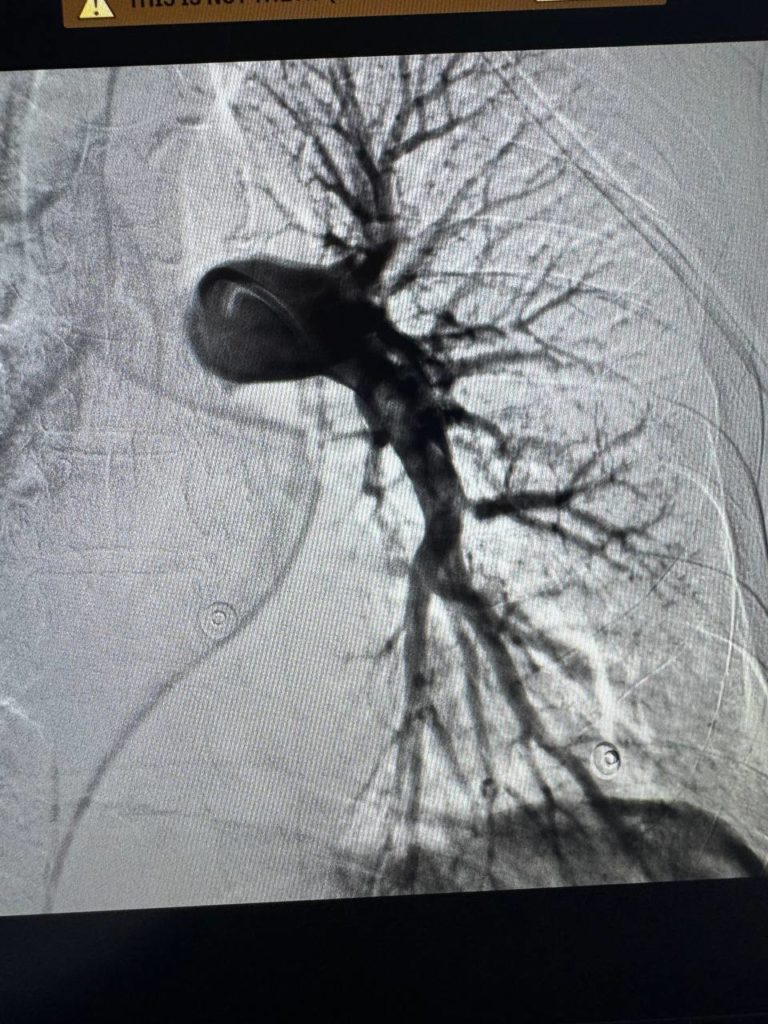

Єдиним шансом на порятунок стало ендоваскулярне втручання — через судину під контролем рентгену. Команда інтервенційних кардіологів, анестезіологів і реаніматологів виконала тромбаспірацію. Це сучасне малоінвазивне втручання, яке дозволяє механічно видалити тромб без відкритої операції. Цей метод лікарі Першого медичного об’єднання Львова опанували під час міжнародного конгресу інтервенційних радіологів у Барселоні і застосовували вперше.

“Це перші успішні тромбаспірації при ТЕЛА, виконані у нашому медоб’єднанні. Ми довели, що Львів має не лише серце, яке допомагає, але й серця, які рятують”, — наголошує завідувач відділення кардіології та реперфузійної терапії Центру серця та судин Лікарні Святого Пантелеймона Василь Процько.